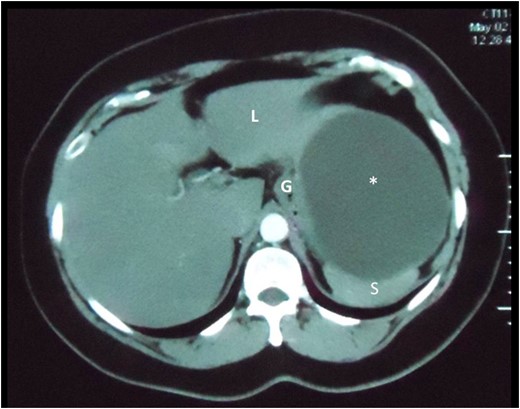

Axial slice of a CT scan demonstrating the cystic lesion that is intimately related to the spleen (S), gastric body (G) and liver (L). A clear plane between the cyst and these organs cannot be demonstrated.